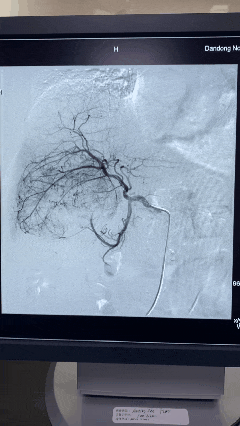

介入科主任姜政伟迅速组织科室医疗团队评估病情,经过充分讨论和科学研判,最终决定实施“肝脏肿瘤供血动脉灌注栓塞术”治疗。手术中,在先进的数字减影血管造影机(DSA)引导下,治疗团队精准找到肿瘤的供血动脉,通过一根纤细的导管将栓塞剂精准送达出血点,像“堵洪水”一样阻断出血源头。整个手术治疗不到1小时就顺利完成,仅在腹股沟处留下一个针眼大小的创口。

术中栓塞前DSA造影图像

栓塞后DSA显示肿瘤出血完全停止